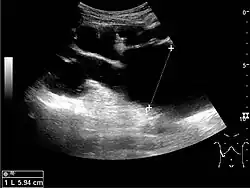

The hydronephrosis is typically graded visually and can be divided into five categories going from a slight expansion of the renal pelvis to end-stage hydronephrosis with cortical thinning (Figure 15). The evaluation of hydronephrosis can also include measures of calyces at the level of the neck in the longitudinal scan plane, of the dilated renal pelvis in the transverse scan plane and the cortical thickness, as explained previously (Figure 16 and Figure 17).[1]

If the fluid in the dilated collecting system has echoes, pyonephrosis should be excluded by clinical exam, blood analysis and, in special cases, puncture or drainage. Hydronephrosis can also be caused by non-obstructive conditions, such as brisk diuresis in patients treated with diuretics, in pregnant women and in children with vesicoureteral reflux.[1]